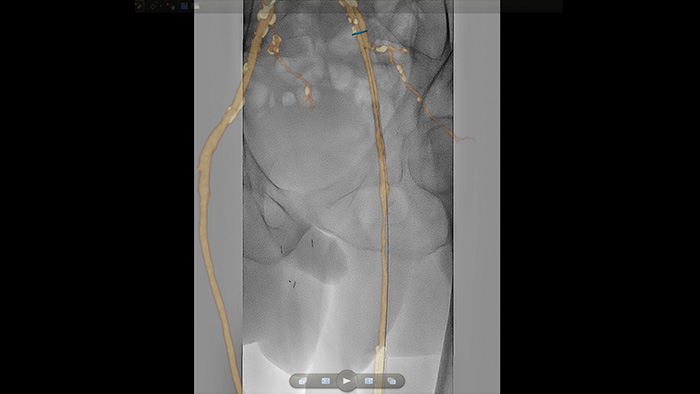

VesselNavigator bietet eine intuitive und fortlaufende 3D Roadmap basierend auf vorhandenen CT-Angiographie- und MRA-Datensätzen, um Sie bei peripheren Verfahren durch das Gefäßsystem zu führen.

Hochauflösende Bilder von Gefäßen mit hervorragender Detailgenauigkeit zur Unterstützung durchdachter Behandlungsstrategien, präziser Navigation und Verlaufsbeobachtung.